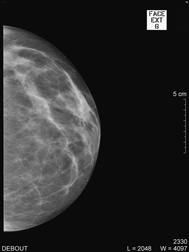

| MAMMOGRAPHIE |

| Debout, le sein légèrement comprimé, deux clichés sont réalisés de face et en oblique sur chaque coté ; d’autres clichés localisés pour mieux analyser une zone peuvent aussi être effectués. |